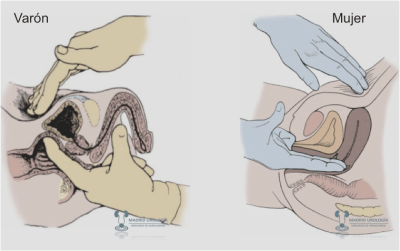

TACTO BIMANUAL BAJO ANESTESIA *

Indispensable para un correcto estadiaje clínico distinguiendo clínicamente una NMVMI de una NMVNMI con una fiabilidad semejante o aún mayor a la del TAC. El Tacto Bimanual (TB) también nos podrá orientar sobre la resecabilidad de la vejiga una vez establecido el diagnóstico de una NMVMI.

Indispensable para un correcto estadiaje clínico distinguiendo clínicamente una NMVMI de una NMVNMI con una fiabilidad semejante o aún mayor a la del TAC. El Tacto Bimanual (TB) también nos podrá orientar sobre la resecabilidad de la vejiga una vez establecido el diagnóstico de una NMVMI.

El TB deberá hacerse antes y después de la RTU V.

| El tacto bimanual en el varón se realiza a través del recto y en la mujer a través de la vagina. |